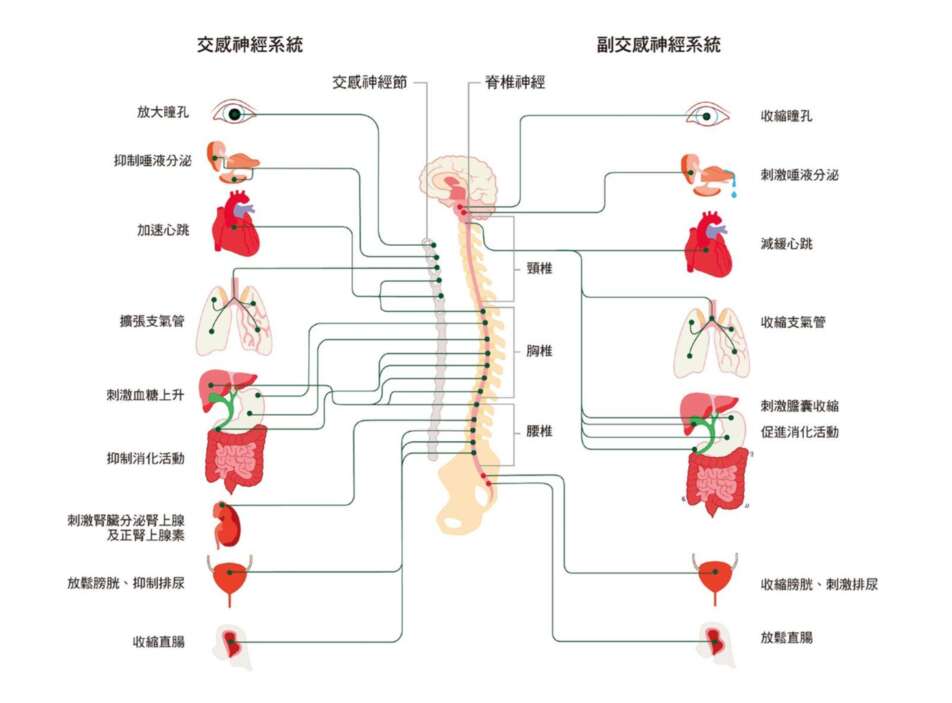

我在《真原醫》和《靜坐》等其他作品也談過皮質醇,又稱「壓力荷爾蒙」(stress hormone)。你應該也可能記得,身體有一個很完整的神經系統,我們通常會稱為自律神經系統,它本身是獨立運作,調控許多生理功能,例如消化、心跳、呼吸、視力的調整、肌肉的收縮放鬆、排洩等等。自律神經系統又可以再細分成兩個子系統,也就是我常說的交感和副交感神經系統。

其中,交感神經系統是幫助我們面對生存的考驗,讓肌肉收縮,呼吸和心跳加快……隨著一天開始,我們要面對種種的事,身體的交感神經系統也就啟動了。交感神經的活化,讓我們加強每一個部位的機能,活力變高,代謝加快。同時,讓我們覺得自己是清醒的。清醒的程度,是在早上10點達到高峰,而反應速度則是在下午3點達到最佳表現。

03 回到交感和副交感神經的作用

如果你讀到科學的專業名詞,心裡就會不由自主縮一下,那麼,看到這個標題,會再萎縮一下,是很正常的,不用擔心。任何人一聽到這種專業的學術用語,其實都會萎縮。值得分享的是,萎縮就是交感神經緊張的作用。如果你現在體會到了自己的萎縮,那麼,表示你已經從身體的每一個細胞懂了什麼是交感神經的過度刺激。

前面提到人體有一個獨立的自律神經系統在調控各種基本的生理功能,例如心跳、呼吸、消化、排洩等等。一般認為,這是腦部最原始的部分,是所有動物都有的基礎運作。無論動物或人類,為了進一步保住生存,都需要把注意力擺到眼前比較緊急的事件,特別是會動的東西(例如眼前的蛇或野獸)。那麼,把基本的生理運作交給一個獨立的自律神經系統,也就好像把注意力從身體最基本而重複的機能抽出來。讓這些基本運作透過固定的神經迴路,落在注意力的背景裡自己運行,大腦才有充分的時間面對環境帶來的變化。

值得一提的是,正是大腦有了這樣的餘裕,才能把學習、認知等等「高等」的運作交給大腦,而讓中腦和小腦負責這種「基礎」(也有人說「低等」)的自動運作。大腦把注意力集中在高等的運作,尤其是透過人類最擅長的記憶和學習的累積,而使得人類截然不同於其他動物。也就這樣,才產生了種種「人類的特質」,包括各種道德、價值觀。

自律神經系統,前面提過又可以區分成交感神經和副交感神經系統。交感神經系統和副交感神經系統一旦失衡,影響會特別大,從出不出汗、體溫高低、心跳快慢、呼吸深淺、消化、排洩、眼睛對光線的反應、肌肉是繃緊還是放鬆,沒有一個角落不受影響。

交感神經系統,是來支持我們行動的動力,同時也帶來緊張和萎縮。用神經科學的語言來說,也就是讓人進入「打或逃」的反射——面對威脅,我們不是打就是逃跑。舉例來說,如果有人去嚇一隻狗,這隻狗要不逃走,要不朝人撲上來,只有打或逃兩種反應。然而,狗的交感神經必須完全啟動,才能引發這兩種反應,而可以得到生存。

因此,交感神經系統又被稱為「壓力反應系統」,讓我們在遇到緊急狀況時,先放掉不那麼急迫的生理功能,例如消化,而全心全意地應付壓力。前面談過皮質醇是壓力荷爾蒙,也就是在內分泌的層面幫助擴大壓力的反應。然而,副交感神經系統的作用是剛好相反,就像是在危機過後的空檔,幫助身體放鬆下來,準備休養生息,也是生存所不可或缺。

可惜的是,這幾十年透過知識的發達,加上資訊傳遞的方便,反而是我們自己生活的步調變成了最大的威脅,隨時變成一種考驗。現代人的生活幾乎無處不是壓力。一醒來,要為了工作、學業、人際關係等等成天忙不完的事而煩惱。我們的工作時間很長,難得有時間好好吃飯、休息,即使夜裡要入睡了,也還有煩不完的心事。這使得我們長時間處在交感神經負荷過重的狀態,原本在危急時刻救命的「打或逃」反射,已成了現代生活最習以為常的運作模式。我過去才會不斷強調,交感的過度刺激是我們二十一世紀最大的身心失衡的原因。

我們透過這種快速的刺激,不光是身心失衡,而很明顯受到影響的部位,也就是消化系統。仔細觀察,在這種快步調的生活中,幾乎每個人的消化都不正常。胃腸道的問題,對現代人是特別普遍的困擾。

交感神經的緊繃,和副交感神經的放鬆,都是我們生存所需要的。然而,現代社會的步調太快,我們念頭太發達,不是還在為過去困擾,好像過去的危機還在眼前,就是為下一步操心,彷彿隨時要面對威脅。可以說,對交感神經的刺激,幾乎沒有一刻停止過。

或許以後,有人再談到交感神經系統、皮質醇、壓力的作用時,你也會有自己心裡的一個畫面,可以表達這些基本的功能。你已經明白,這種壓力反應,從史前的原始人,到現代穿西裝打領帶的人,都一樣逃不掉的。它本身既是我們最大的一個生存功能,卻也同時成為現代人最大的危機和威脅,也就解釋了我們為什麼會失眠。

壓力,本身會提高交感神經系統的作用,讓我們全身緊張,也自然導致失眠。這兩者是惡性循環。我才會認為要解決失眠的問題,首先要從降低交感神經的作用去著手。

一個人假如長期失眠,交感神經隨時在活化,等於無時無刻都處於過度的刺激,面對樣樣現象和人事物,反應和認知自然都很緊繃。反過來,一個人假如隨時處在高壓力的狀況下(這其實是我們每一個現代人離不開的狀況)自然也難免刺激交感神經系統過度作用,回過頭來也得不到睡眠。

從我個人的看法,睡眠,通常要透過放鬆,才可能達到,而這是副交感神經的作用。對現代人,需要的反而是找出一個活化副交感神經系統的鑰匙。這一點,才是讓我們回到均衡,甚至解答睡眠問題的關鍵。